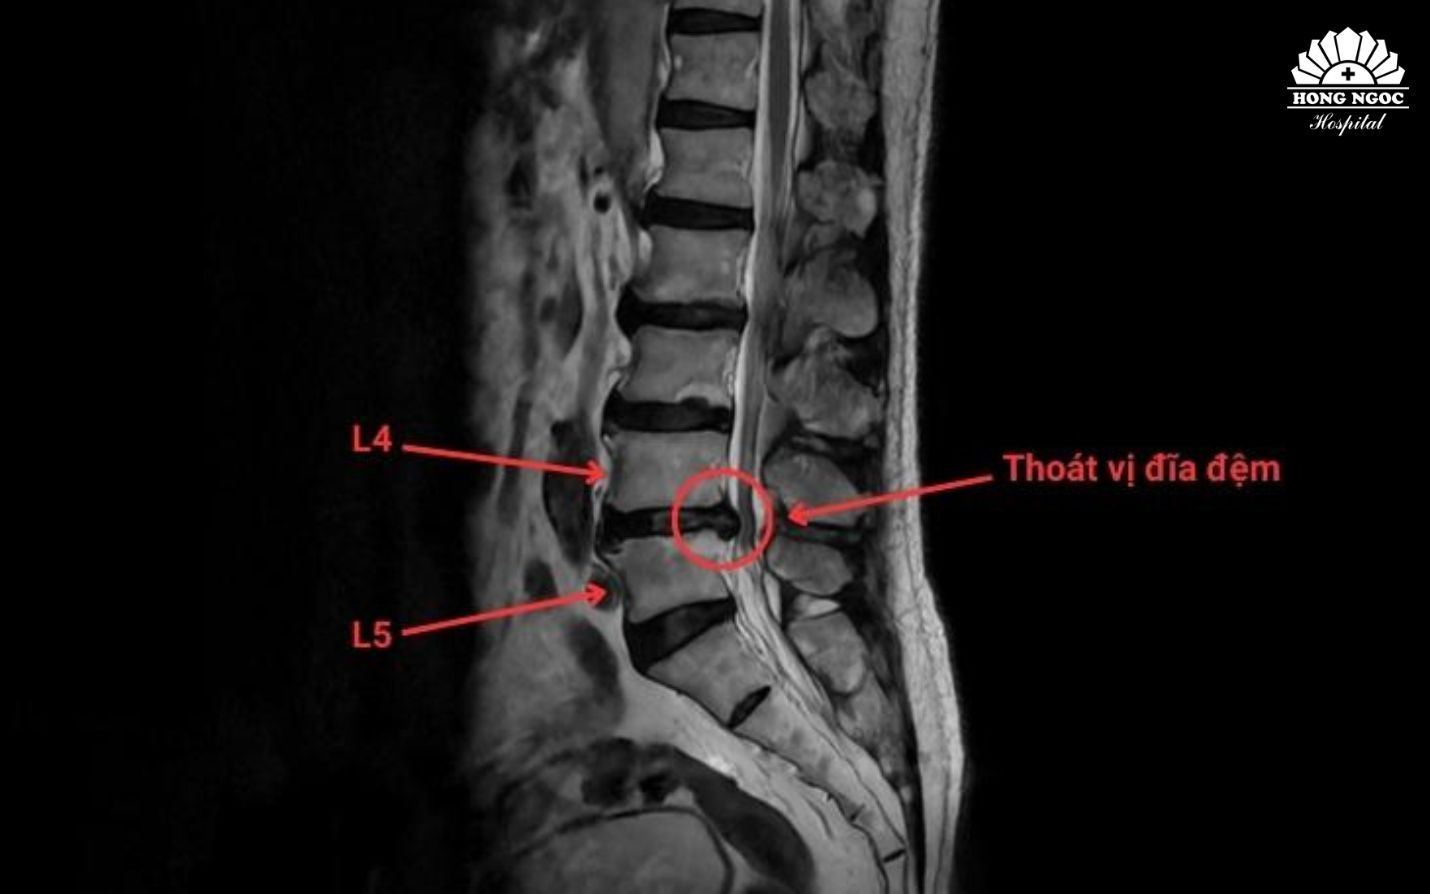

TS.BS Trịnh Tú Tâm (Trưởng khoa Chẩn đoán hình ảnh và Điện quang can thiệp, BVĐK Hồng Ngọc - Phúc Trường Minh) cho biết: Thoát vị đĩa đệm là tình trạng nhân nhầy thoát ra khỏi vị trí ban đầu qua vết rách bao xơ, chèn ép vào rễ thần kinh và gây nên những cơn đau cấp và mạn tính. Trong điều trị, các phương pháp can thiệp điện quang ít xâm lấn đang trở thành xu hướng hiện đại, được áp dụng rộng rãi tại nhiều quốc gia trên thế giới. Dưới hướng dẫn của hệ thống chẩn đoán hình ảnh, bác sĩ can thiệp tiếp cận chính xác vị trí tổn thương để xử lý nhân nhầy hoặc giảm chèn ép rễ thần kinh mà không cần phẫu thuật mở. Phương pháp này giúp điều trị tận căn nguyên, giúp giảm đau nhanh, phù hợp với người cao tuổi hoặc có nhiều bệnh lý nền.

TS.BS Trịnh Tú Tâm phân tích: Can thiệp điện quang giảm đau là phương pháp điều trị thoát vị đĩa đệm cột sống bằng kỹ thuật ít xâm lấn, không cần phẫu thuật mở. Phương pháp này phù hợp với bệnh nhân thoát vị đĩa đệm cổ hoặc thắt lưng đã điều trị nội khoa, vật lý trị liệu hay phục hồi chức năng không còn hiệu quả, cũng như những trường hợp đau tái phát sau phẫu thuật. Các chỉ định thường áp dụng cho thoát vị đĩa đệm mức độ nhẹ đến trung bình, khi vòng xơ chưa rách hoặc chỉ rách nhỏ, chiều cao đĩa đệm còn trên 50% và khối thoát vị không vượt quá một phần ba đường kính ống sống. Ngoài ra, đây còn là lựa chọn an toàn cho người cao tuổi hoặc bệnh nhân có nhiều bệnh lý nền, không đủ điều kiện thực hiện phẫu thuật.